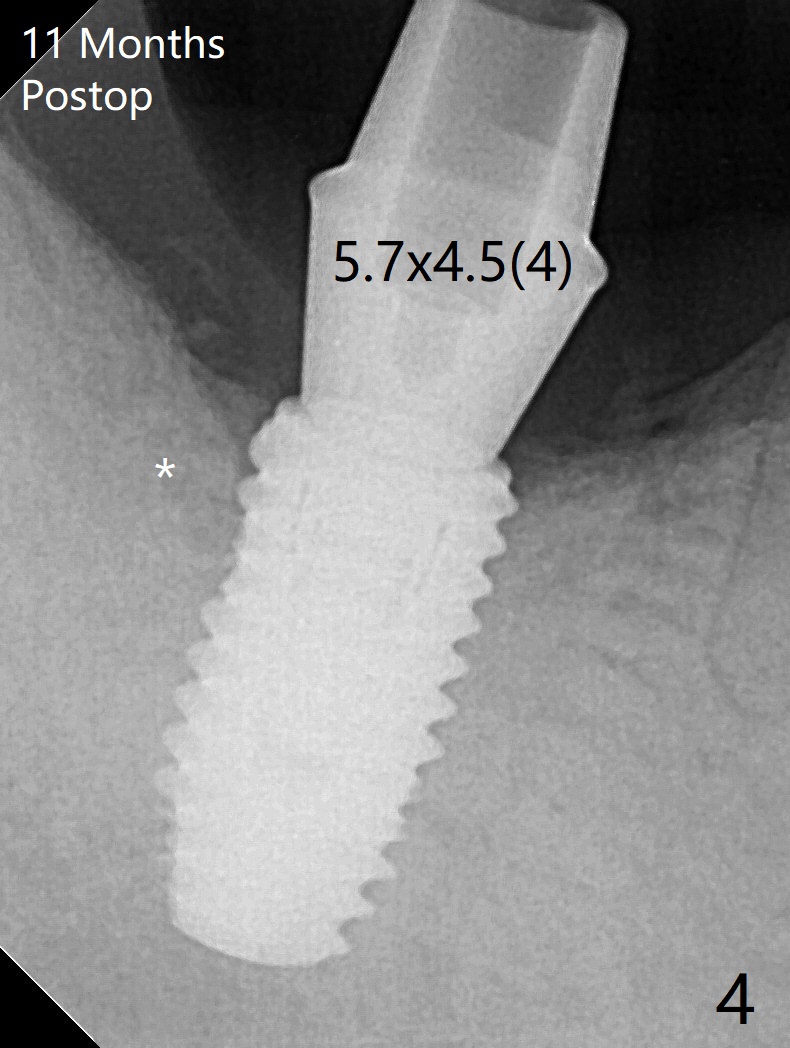

The morning case shows that to avoid Inferior Alveolar Neuropathy associated with 2nd molar implant placement, three measures should be adopted, no block anesthesia, no pressure on the distal end of the distal end guide and no over deep placement. In fact pain control is difficult with severe chronic periodontitis at #31. After repeated infiltration injection, the most effective step of anesthesia is slow speed of osteotomy with gentle pressure. The 1st intraop PA is taken when the depth is reached with a 2.2 mm pilot drill (Fig.1 (yellow dashed line: superior border of the Inferior Alveolar Canal)). The 2nd purpose of the PA is to make sure that the osteotomy is establish in the mesial slope of the socket (red dashed line). As drills increase in diameter, the patient experiences pain. Since the bone density is high, it is hard to place 5x10 mm implant to the lowest space (Fig.2 *, ~ 60 Ncm). For compensation, bone graft (Fig.3 *) is packed securely around the implant before and after abutment insertion. After fabrication of an immediate provisional, periodontal dressing is applied around the provisional and socket to prevent graft leakage. Smoke cessation/reduction is encouraged. In fact the patient returns 11 months postop (the 1st time postop), partly due to coronavirus. The immediate provisional is lost, but the distal defect has apparently been repaired (Fig.4*). A 4 mm cuff abutment is changed to due to enough occlusal clearance. The abutment is completely seated. Oral hygiene is poor with 1/2 ppd of smoke. SRP was done in the lower right quadrant when the implant was placed. When the crown is delivered 1 year postop, the patient mentions #18 mobility. SRP is done in the lower left quadrant. The bone is stable 10 months post cementation (Fig.5).